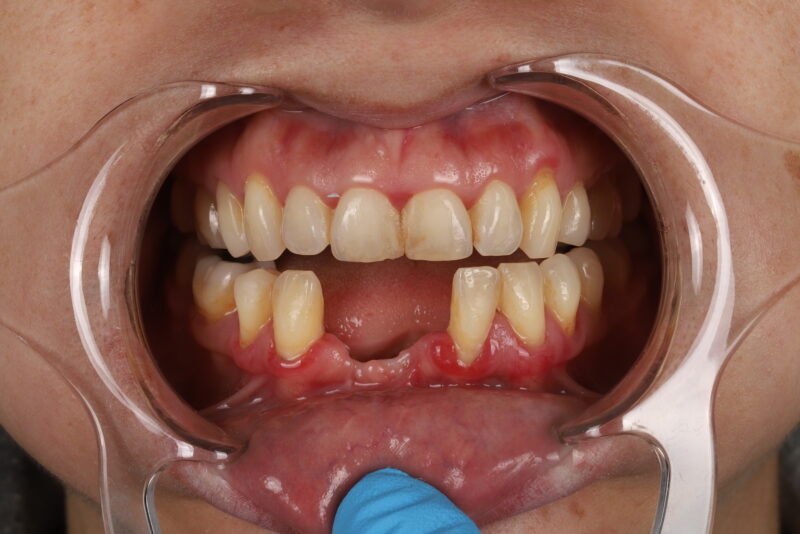

• intraoral pic

• I would remove them both and start over. The only way I’d restore 3 is if it was aware that it had less than 5 year prognosis. The issue was tissue thickness which was less than 2mm thick in all dimensions. I would just be honest with pt that their bone didn’t heal well and you’re concerned about long term prognosis. If they were hell bent I…

Read more